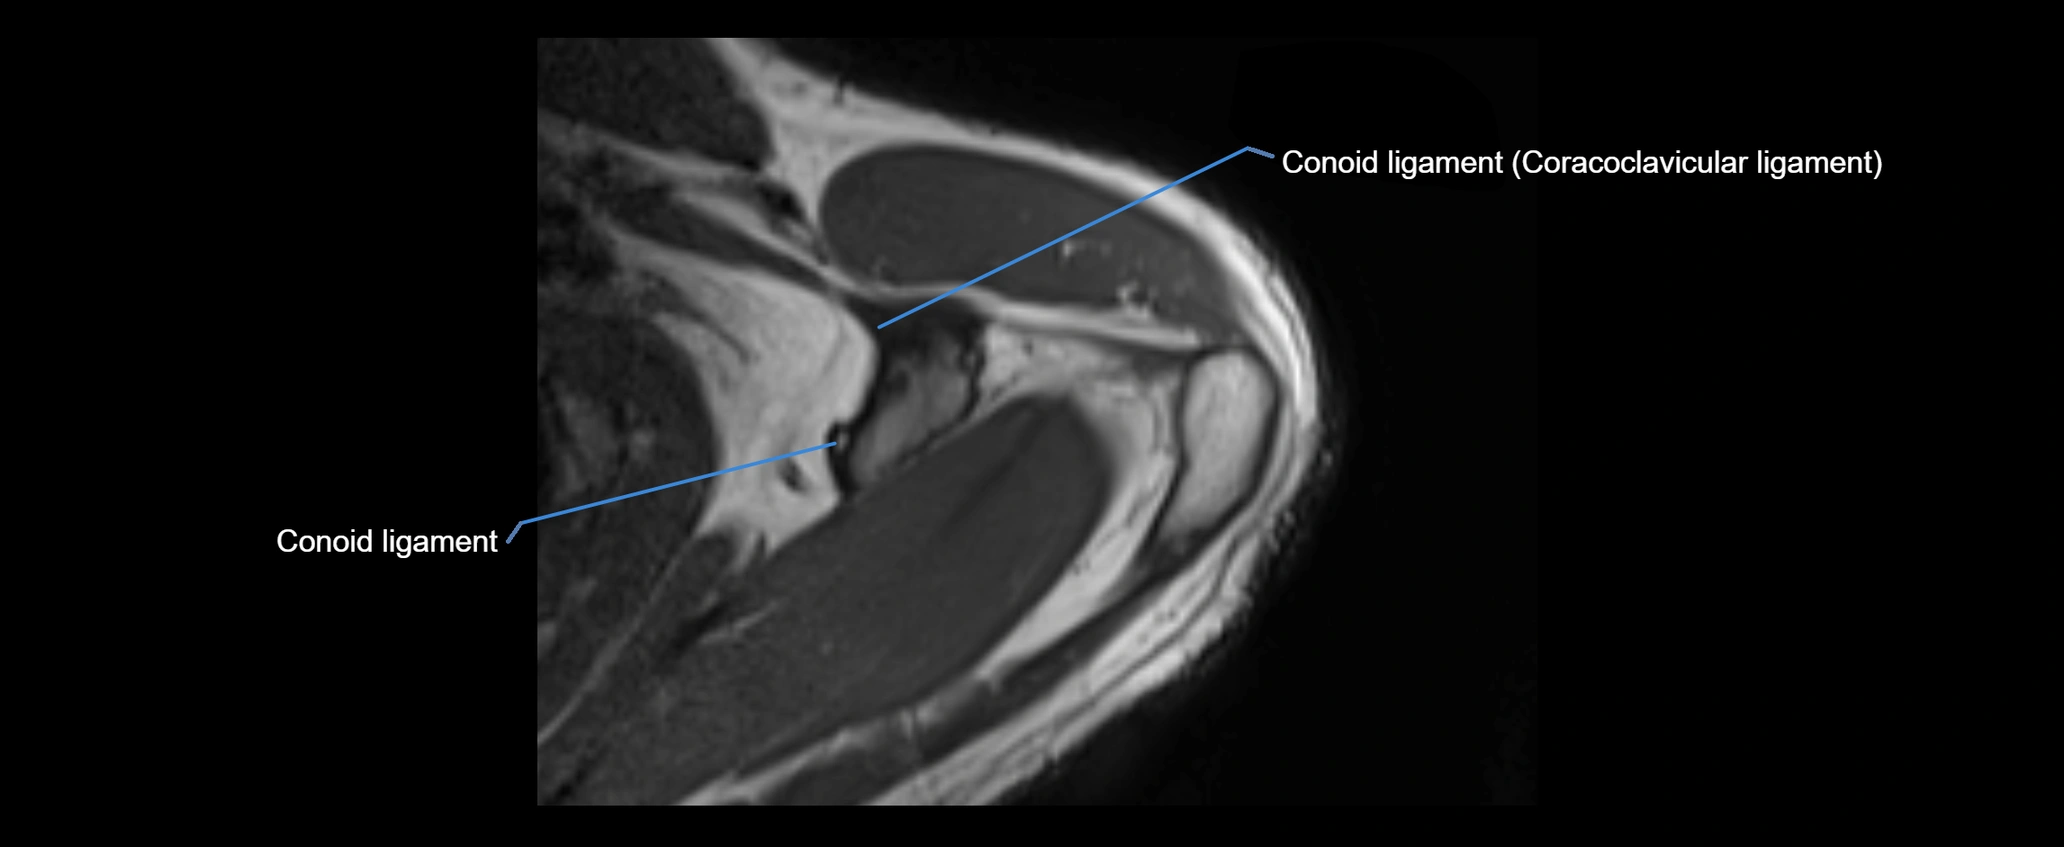

CT image

image